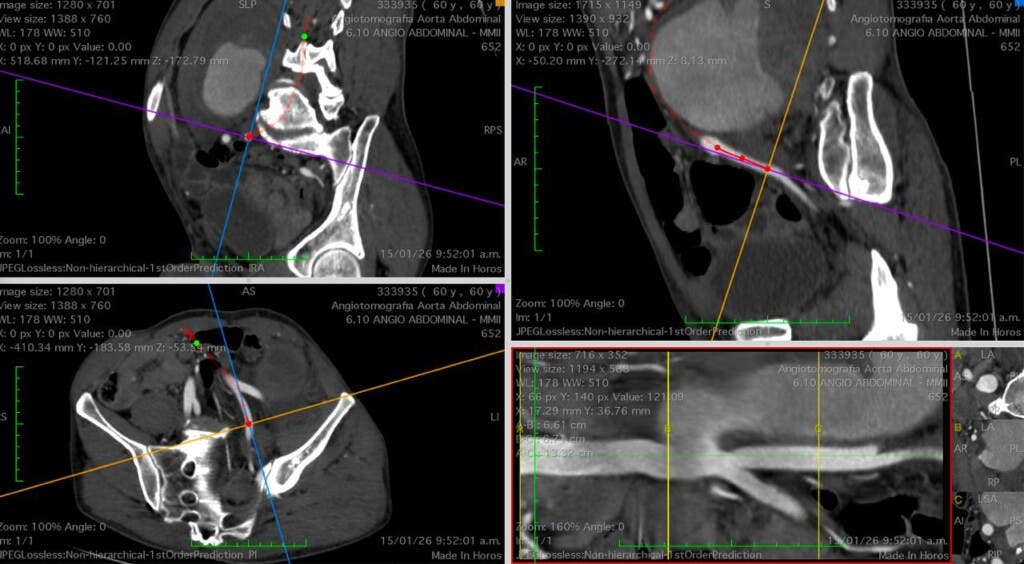

Como ejemplo, citó los casos de aneurisma de la aorta abdominal, una condición silenciosa y letal si no se trata a tiempo. Indicó que la intervención requiere una prótesis especial de politetrafluoroetileno (PTFE), cuya autorización ha sido negada en reiteradas ocasiones, según su denuncia.

«Cuando un aneurisma se rompe, el paciente muere por hemorragia interna. Negar esa prótesis es prácticamente dictar una sentencia de muerte», advirtió.